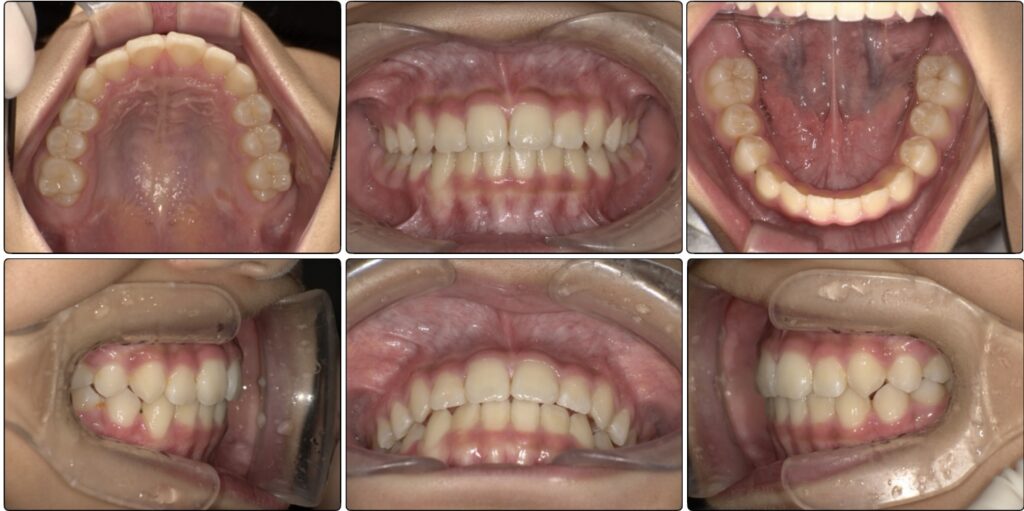

現在

前歯も生えてきたのですが2番目の歯の隙間はなく後ろから生えてきています。

ですがこれはマウスピースとアクティビティーでここまで綺麗に入りました。

歯並びも良くなってきていますが、まだアーチは完全なUの字にはなっていません。

3ヶ月頃で外すのですが、しっかり前歯が並んできています。

ですがまだ3番目の歯が入る余裕はない状態です。

今はしっかり綺麗な噛み合わせになっています。